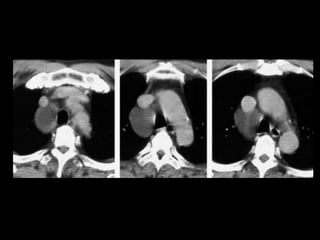

Sequestro intralobar com infecções recorrentes

Sequestro intralobar cominfecções recorrentes